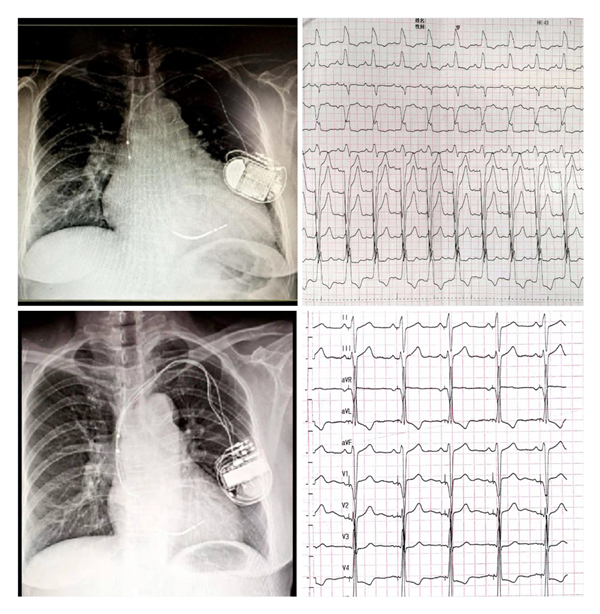

华体会体育官方网站 为国内较早开展左束支起搏(LBBP)的中心之一,自2018年1月开展福建省首例LBBP以来,至今累计例数已近200例。中心采用黄伟剑教授的标准术式,手术成功率高、并发症少,随访导线参数稳定。此前起搏团队为1例外院CRT失败转诊华体会体育官方网站 的患者实行左束支起搏治疗得到了良好的疗效,LVD从80mm 缩小至52mm,LVEF 从24%升高至60%,心脏完全恢复正常。目前华体会体育 常规开展这一技术以造服更多的心衰患者。

(上图左上为CRTD术前,外院植入ICD2年,右上是自身完左心电图;左下为CRTD术后一年,右下为CRTD术后心电图)